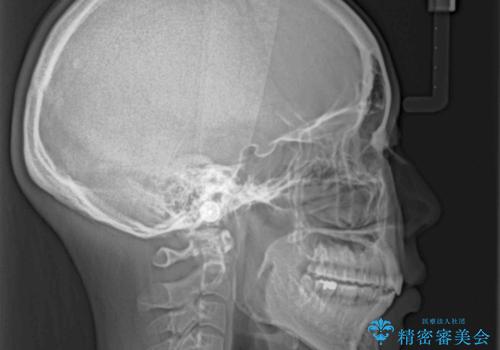

前歯のデコボコを抜歯矯正で改善 メタル装置で費用を抑える

- 前歯のデコボコと口元の突出感を気にして来院された患者様です。

非抜歯矯正ではデコボコを解消することでより口元が突出してしまうため、上下左右の小臼歯4本の抜歯を行い、ワイヤー装置による矯正治療を行うこととしました。

もう少し口元の突出感を改善したかったのですが、舌の突出癖が影響し下顎前歯が唇側に押させる仕上がりとなりました。